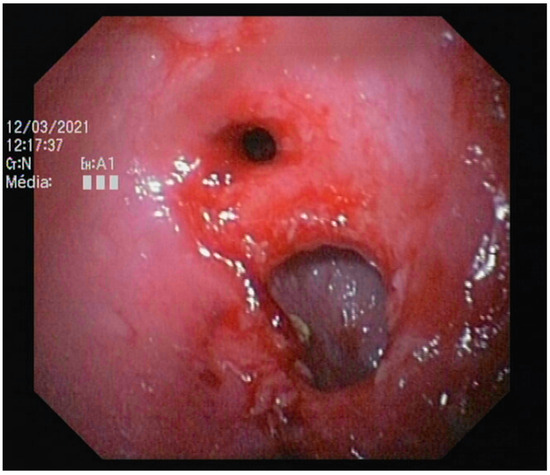

3.2.4. Endoscopic Findings

| Endoscopic Findings | Number | Percentage (/20 Endoscopies) | Number | Percentage (/20 Endoscopies) | p Value (Chi-Squared Test) |

| Ileocolic junction abnormalities | 4 | 20% | 4 | 20% | 1 |

| Stenosis | 10 | 50% | 2 | 10% | <0.001 |

| Macroscopic erosion | 1 | 5% | 4 | 20% | <0.001 |

| Nonspecific mild to moderate colopathy | 5 | 25% | 3 | 15% | 0.077 |

| Unremarkable | 1 | 5% | 1 | 5% | 1 |